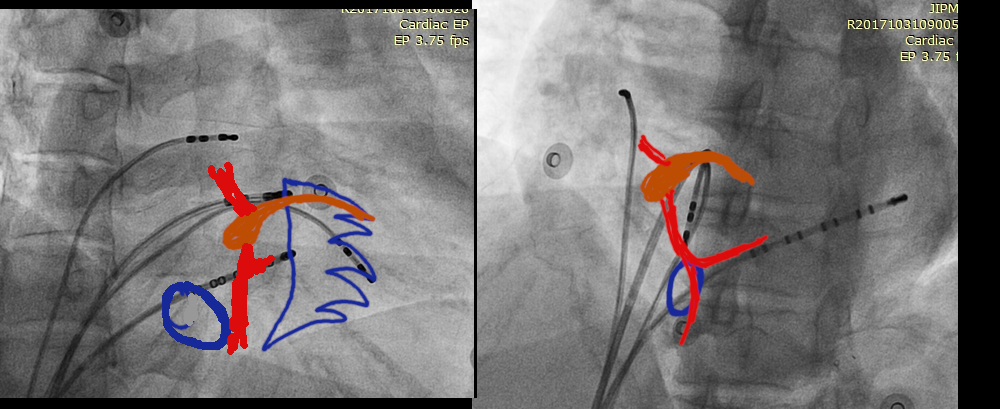

Left side ablation

lao_rao.jpg

LV_signals.jpg